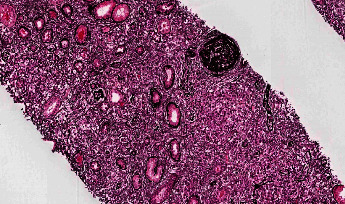

IgG4-related disease (IgG4-RD) is an immune-mediated disorder marked by fibro-inflammatory masses that can infiltrate multiple organ systems. Due to its relatively recent discovery and limited understanding of its pathophysiology, IgG4-related disease may be difficult to recognize and is consequently potentially underdiagnosed. Renal involvement is becoming regarded as one of the key features of this disease. To date, the most well-recognized renal complication of IgG4-related disease is tubulointerstitial nephritis, but membranous glomerulonephritis, renal masses, and retroperitoneal fibrosis have also been reported. This concise review has two objectives. First, it will briefly encapsulate the history, epidemiology, and presentation of IgG4-related disease. Second, it will examine the reported renal manifestations of IgG4-related disease, exploring the relevant histology, imaging, clinical features, and treatment considerations. This synthesis will be highly relevant for nephrologists, rheumatologists, general internists, and renal pathologists to raise awareness and help improve early recognition of IgG4-related kidney disease (IgG4-RKD).